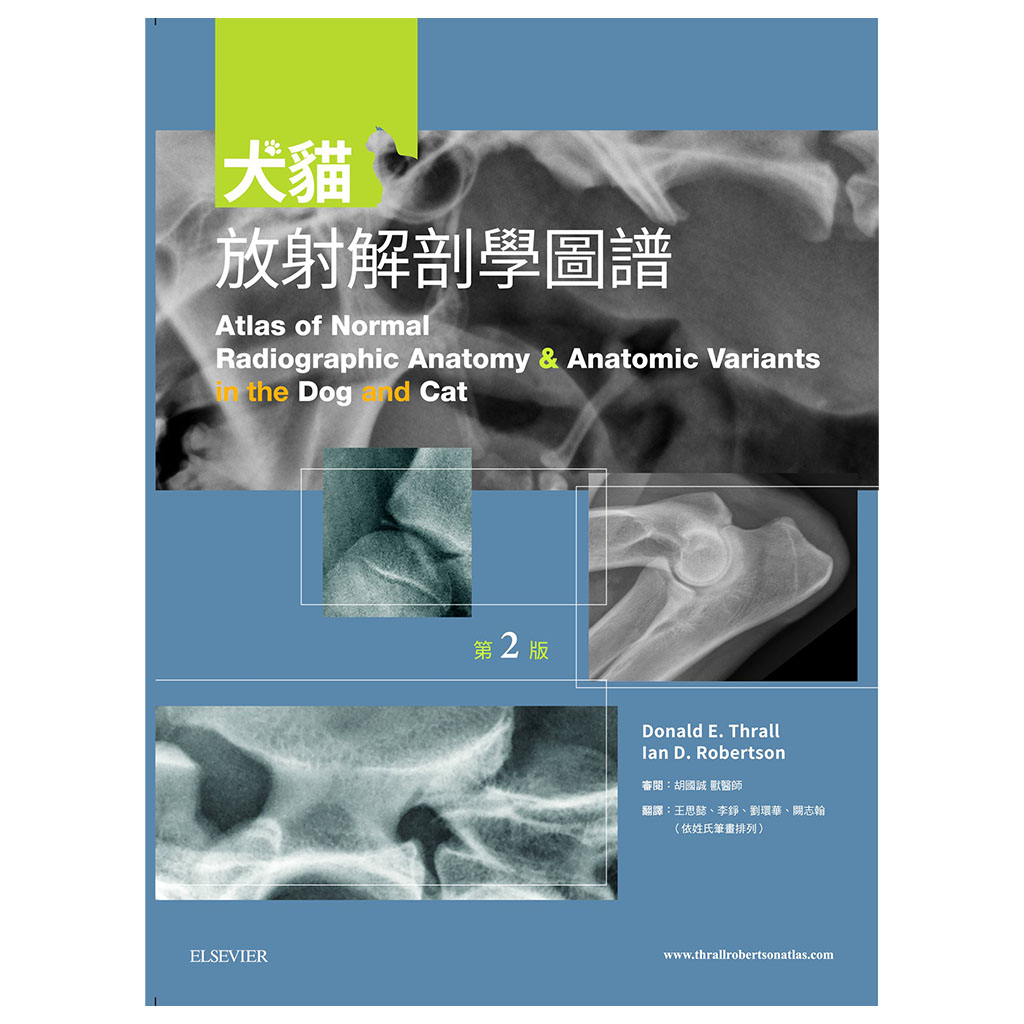

犬貓放射解剖學圖譜(2版)

Atlas of Normal Radiographic Anatomy and Anatomic Variants in the Dog and Cat

作者: Donald E. Thrall, Ian D. Robertson, 胡國誠

譯者: 胡國誠, 王思懿, 李錚, 劉環華, 闕志翰

出版社:台灣愛思唯爾

出版日期:2017/11/28

語言:繁體中文

ISBN:9789869548519

規格:平裝 / 308頁 / 21 x 28.5 x 1.54 cm / 普通級 / 單色印刷 / 2版

出版地:台灣

專為犬貓正常影像的深入判讀,使診斷更精確達到更佳的治療

以這本詳盡的圖譜學習犬貓正常放射線解剖學的範圍。精通本書將可使診斷更精確並達到更佳的治療效果!

全書皆為高對比的數位影像,除提供正常影像的深入判讀外,亦提供常見且易被誤判為疾病的正常變異;另外並提供多張電腦斷層影像以強調某些結構之影像在放射線學下顯得如此獨特的原因。

本書不但含有豐富圖片,身體各部份皆附上文字描述以協助讀者了解放射解剖學原則,讀者可舉一反三、甚至能以此理解未包含於本書的正常變異。

最新!包含問題、解答及解題的伴讀網站,超過一百個加強重要放射線解剖學觀念及著重於正常差異誤判為疾病的問題。

最新!更多的電腦斷層影像,詳細解釋某些結構形成獨特放射線學影像的原因。

最新!提供更廣泛的正常範圍。

最新!提供各品種犬貓之獨特影像。

.詳盡的文字說明及圖片標示

.未標記的原始圖片及標示後的圖片比對